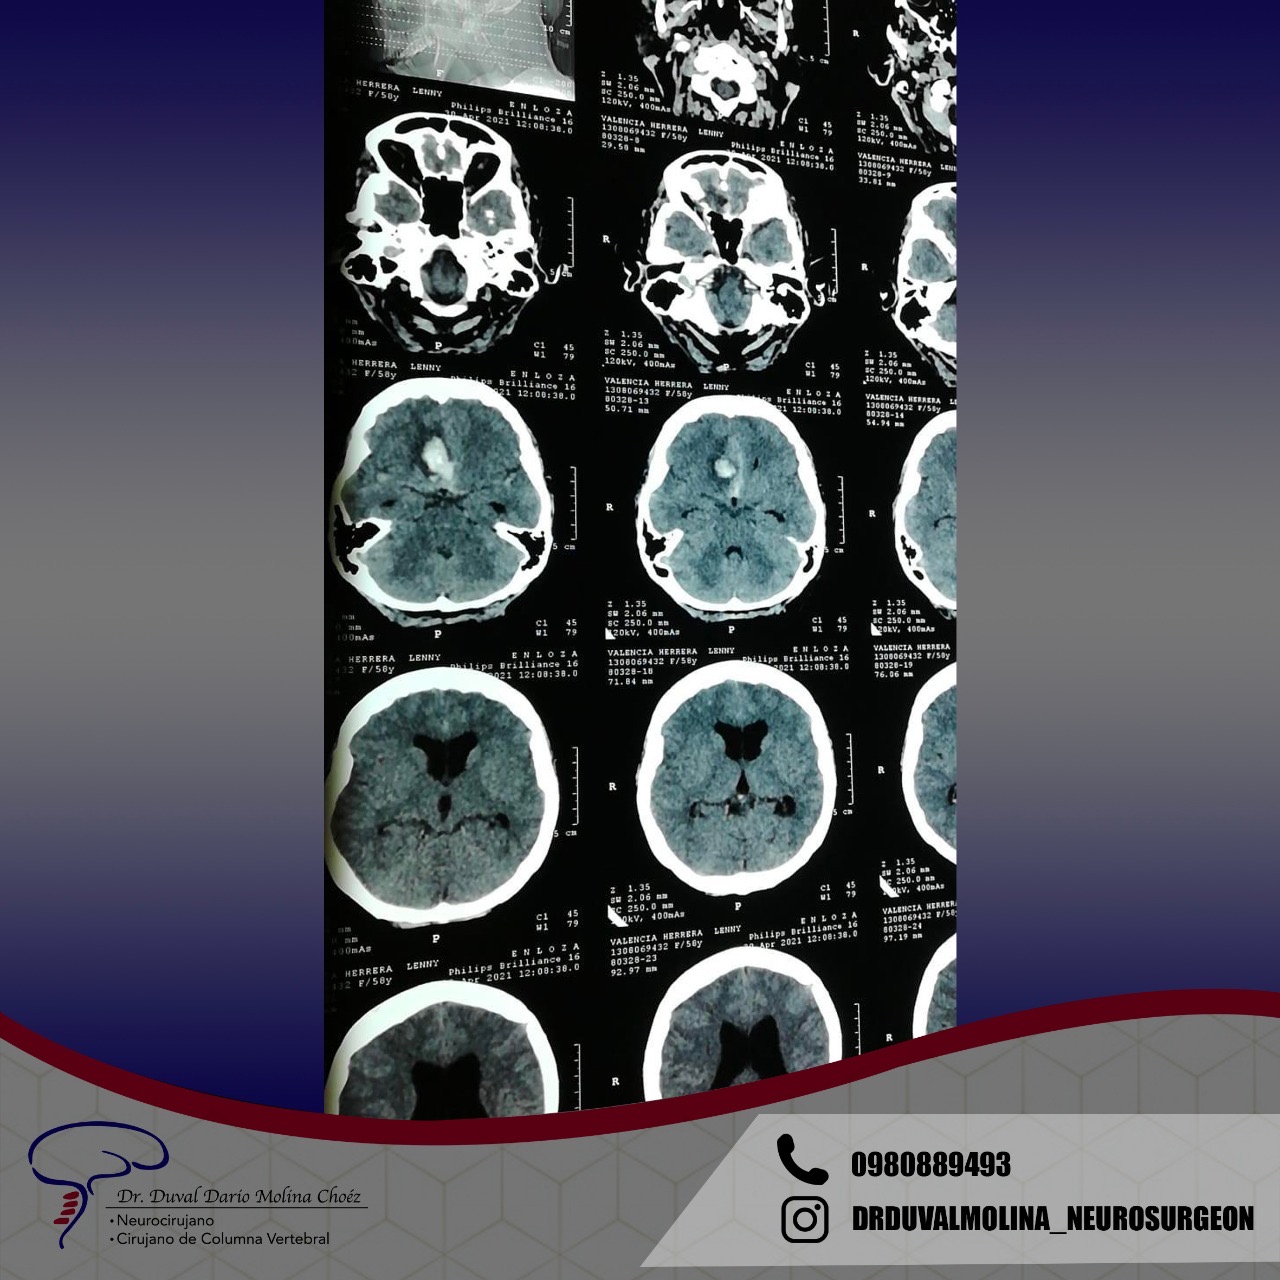

A Glioma that causes compression effects and “edema” (swelling).

Ventriculoperitoneal shunt placed for “hydrocephalus”.